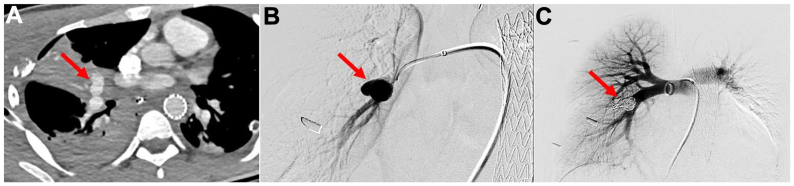

The patient recovered well with distal pulses appreciated in all four extremities. Repeat CTA revealed a 1.9 × 1.0-cm PA pseudoaneurysm for which the patient underwent percutaneous coiling with three 10 mm × 30-cm and two 14 mm × 50-cm interlocking detachable coils (Boston Scientific, Natick, MA) via right common femoral vein access (Fig 4). His fasciotomy was closed on postoperative day 10. He was discharged home on postoperative day 15.

Fig 4.

Repeat computed tomography angiogram demonstrated a large 1.9 × 1.0-cm right pulmonary artery (PA) pseudoaneurysm (PSA) (A) which was confirmed on invasive angiography (B). This was adequately treated with coil embolization with angiogram demonstrating no further pseudoaneurysm sac filling (C). The PSA is identified with red arrows.